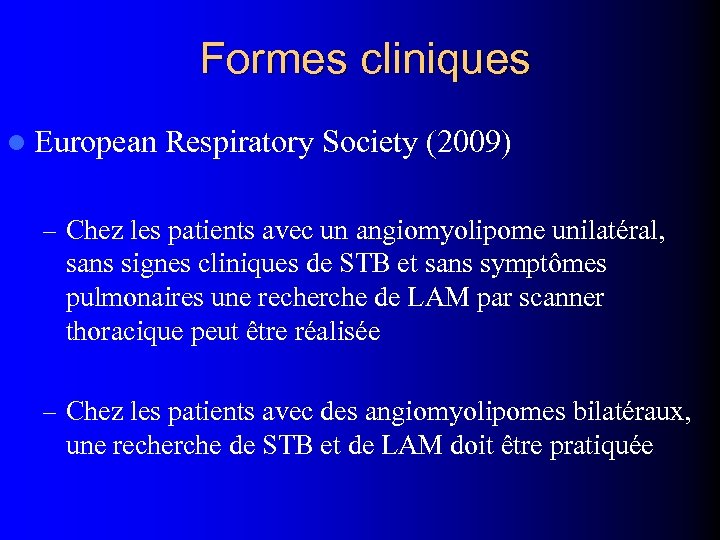

Formes cliniques l European Respiratory Society (2009) – Chez les patients avec un angiomyolipome unilatéral, sans signes cliniques de STB et sans symptômes pulmonaires une recherche de LAM par scanner thoracique peut être réalisée – Chez les patients avec des angiomyolipomes bilatéraux, une recherche de STB et de LAM doit être pratiquée

Formes cliniques l European Respiratory Society (2009) – Chez les patients avec un angiomyolipome unilatéral, sans signes cliniques de STB et sans symptômes pulmonaires une recherche de LAM par scanner thoracique peut être réalisée – Chez les patients avec des angiomyolipomes bilatéraux, une recherche de STB et de LAM doit être pratiquée